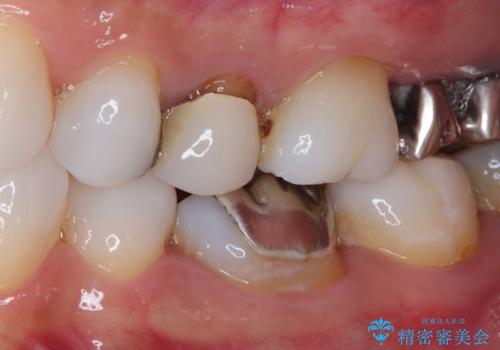

- 奥歯の銀歯とクラウンの縁から見えている歯根を気にして来院された患者様です。

歯根の見えている歯はセラミッククラウンに、詰め物の銀歯が入っている歯はセラミックインレーにて治療を行うこととしました。

笑ったときなど、口を開いたときに目立っていた銀歯や茶色い歯根が気にならなくなり、患者様には大変満足していただけました。